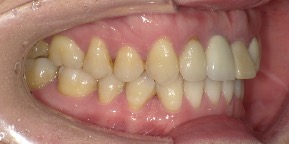

33歳女性のビフォーアフター

| 診断 | 空隙 |

| 治療方針 | 治療方針:前歯の咬合関係改善と空隙閉鎖を主な目的にて主にIPR(歯と歯の間をわずかに削合してスペースを獲得する方法)を組み込んだ動的矯正治療を行い、空隙、前歯咬合を改善後、保定を行う。臼歯部の咬合関係はプランの都合上維持することとした。 |

| 治療費 ※ | 67万8千円(診断、型取り、矯正中のメンテナンス、保定装置を含む料金) |

| 治療期間 | 6か月 |

| リスク | 1日20時間以上マウスピースを使用できない場合、歯が動かなかったり、想定しない誤差により不完全に終わる可能性がある。装着時や食事時に痛みを伴う。歯肉退縮や虫歯になるおそれがある。また、指導通りに装着できていない場合や適切なブラッシングが出来ていないとそのリスクが高くなる。歯根が短くなることがある。ごくまれに歯の神経が損傷してしまうことがある。過去にぶつけたり深い虫歯治療をしたことがあるとそのリスクはやや高くなる。矯正後には保定装置が必要。適切な使用ができない場合、後戻りの原因となる。将来的に歯並びが動いて再矯正が必要な場合がある。親知らずが正常に生えていない場合、その可能性がやや高くなる。 |